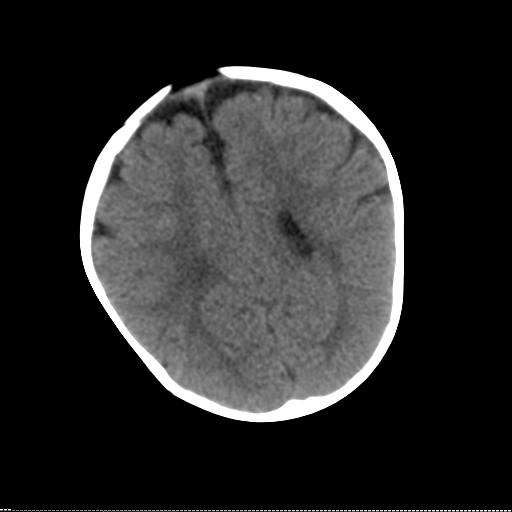

患儿 1岁 不能站立 出牙迟缓。反应尚可,临床怀疑脑发育不良。请各位专家指教。

怎么感觉额颞部脑回增多,皮质增厚,髓质少呢

多脑回畸形?

双侧额叶、颞叶珠网膜下腔、外侧裂池、前纵裂池均增宽,我认为这是较典型的外周性脑积水,大部分患儿到三周岁后能自愈。

沟裂较宽,脑回较粗,白质区减少,定期复查ct片或mri。

如果非要找个异常,我觉得双侧脑室体部间距有些宽,建议mr检查.

对于一个一岁的小儿来说脑沟裂那么宽难道不是异常吗